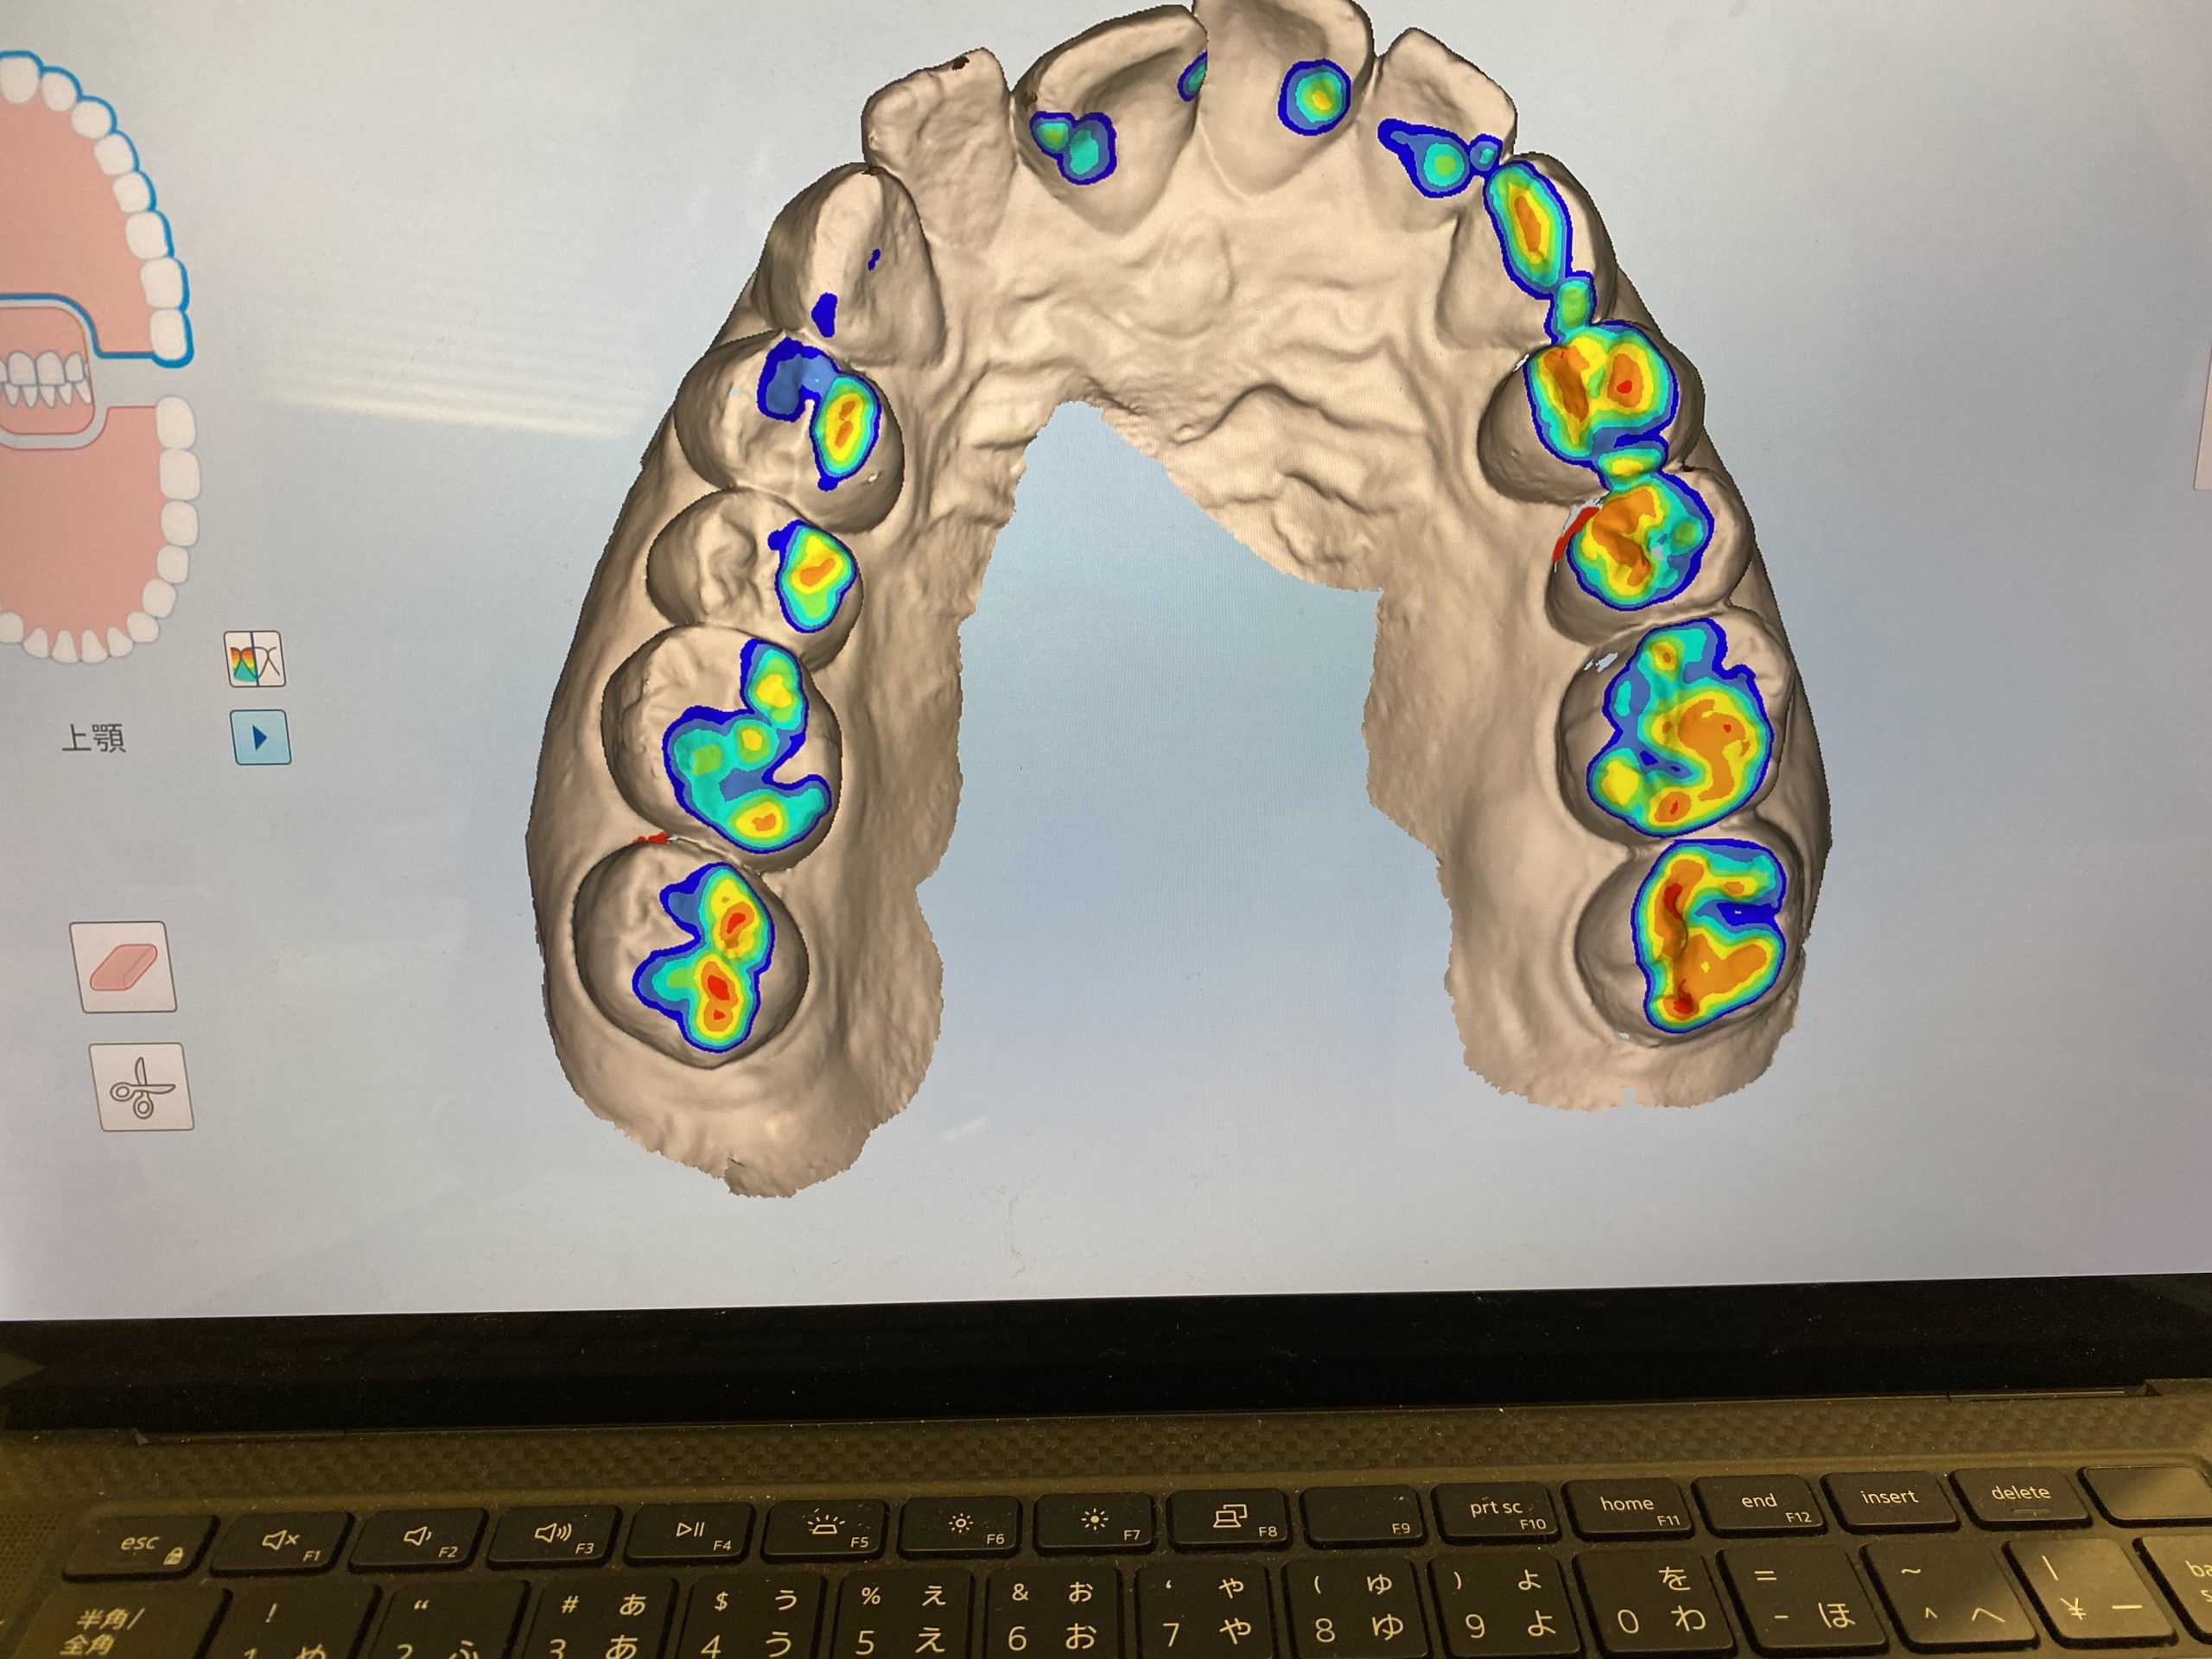

3Dスキャナーで一歩先を行く診療を実現 2022.1.1

単なる口腔内スキャナーではなく

・嚙み合わせの強い所、弱いところなどの咬合診断

・隣接面の虫歯の発見

近赤外光画像(NIRI)技術で歯の内部構造をリアルタイムでスキャンしデータ化します。

普通のレントゲンでは心配という患者様に早期発見に役立ちますね。

矯正だけでなく嚙み合わせが不調の方も先進的な視覚化ツールで患者様は御自身の口腔内状態についてリアルタイムで知ることができます。

私達クリニック側からも、診断と治療のワークフローがよく患者様の石膏模型もスキャンデータでクラウド上に保管できるのも助かります。